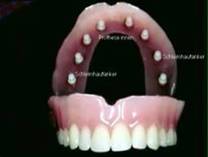

SCHLEIMHAUTANKER nach Dr. Engels Arztpraxis für Zahnheilkunde Am Kurpark 5 53177 BONN - BAD GODESBERG FON: 0228 - 355315 * FAX: 0228-352364 |

Für jedes Patientenalter!, Preisgünstiges System! Sie ersparen sich Haftcreme oder Haftpulver! Von jedem Zahnarzt praktizierbar. Seit 1986 Jahren erfolgreich! Kein grosser chirurgischer Eingriff! Sie können wieder sicher sprechen, essen schwimmen, etc.! Gaumenfrei!Wir benennen Ihnen gerne Zahnärzte, auch in Ihrer Nähe. Weitere Informationen können Sie gerne unterfolgenden Internetadressen anfordern!www.DrEngels.de Oder E-Mail: DrEngels@t-online.de |